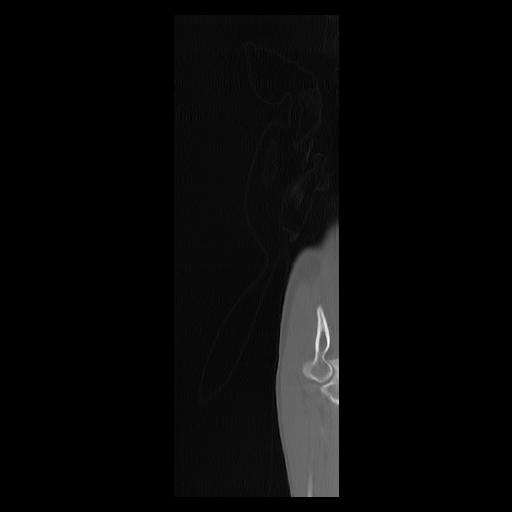

33 PULMON,CE,Sagittal,3.000,PULMON,Sagittal,